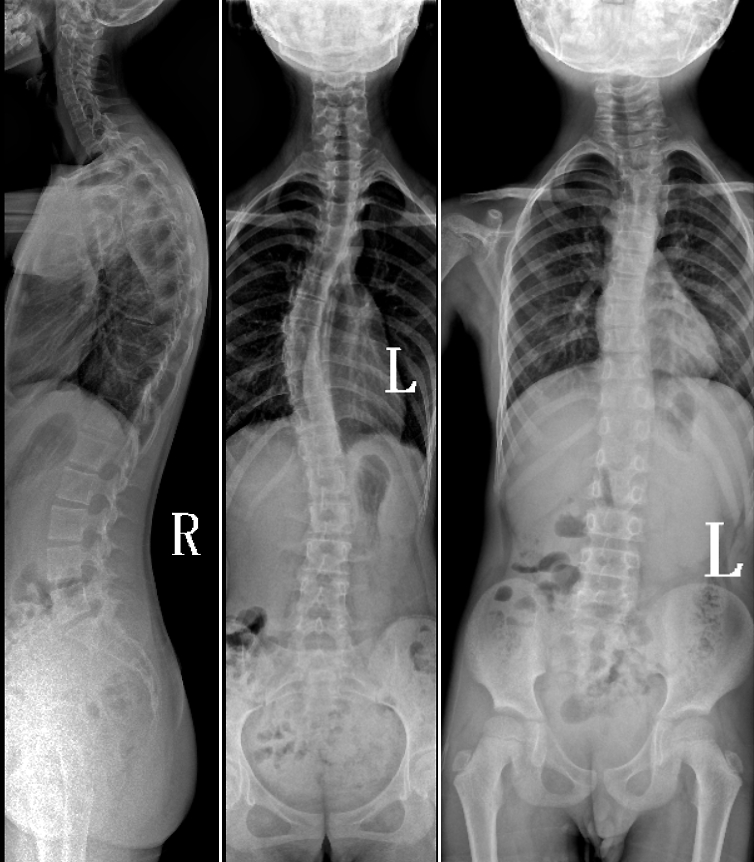

DR是臨床骨科的重要檢查手段之一。在骨科檢查中,脊柱矯形、長骨骨折、腰椎退行性病變等,需要采集脊柱、下肢全景圖像,輔助醫(yī)生臨床診斷,從而制定科學(xué)的治療方案,普愛醫(yī)療的大視野平板動(dòng)態(tài)DR就像是一座橋梁,連接起現(xiàn)代醫(yī)療技術(shù)與當(dāng)?shù)厝嗣竦尼t(yī)療需求。

普愛醫(yī)療自主研發(fā)的大視野平板動(dòng)態(tài),采用17"*34"的有效視野,一次曝光即可得到全脊柱或全下肢影像。相較于多張攝影再軟件拼接的DR設(shè)備,PLX8600解決了拼接圖像存在密度不均勻,拼接處圖像配準(zhǔn)和放大效應(yīng)等問題,給臨床帶來了真正的大視野影像解決方案。